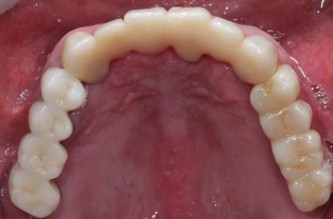

50代 男性

治療前

治療後

治療後- 年齢/性別

- 50代/男性

- 主訴

- 上顎の義歯の具合が悪いため、インプラント希望

- 治療期間

- 1年間

- 治療費

- インプラント¥4,400,000

骨造成¥220,000

サージカルステント¥99,000 - リスク・副作用

- 術後の腫れ・出血